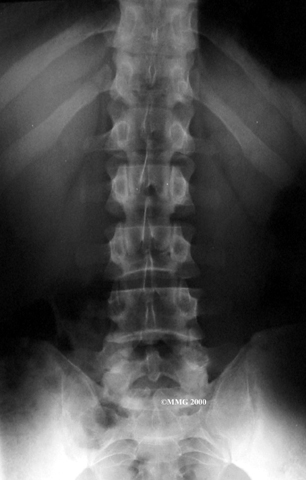

X-rays are of minor help in diagnosing disc herniations. The discs don't actually show up on X-rays. However, doctors can tell if the space between the vertebrae is smaller than normal. This can be an indication that wear and tear on one or more discs is causing problems. However, many peoples' X-rays show degeneration of the discs. This is because degeneration in the discs is part of aging, like skin that wrinkles with time.

X-rays